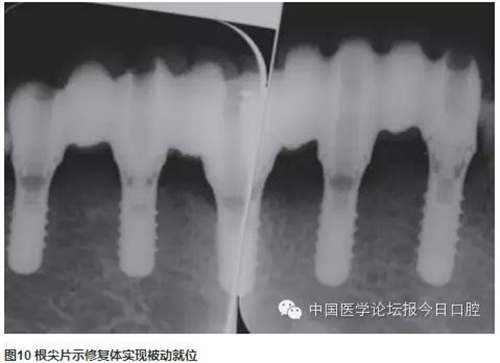

技工室制作純鈦支架,聚合瓷修復(fù)牙齒和牙齦形態(tài),患者口內(nèi)試戴,只將一個種植體的固定螺絲加力,拍片可見其余3顆種植體均實現(xiàn)被動就位,然后將4顆種植體固定螺絲加力,封口(圖2~圖10)。

CAD/CAM螺絲固位固定修復(fù)體就位順利,咬合關(guān)系正常,牙齒與牙齦顏色患者較滿意。